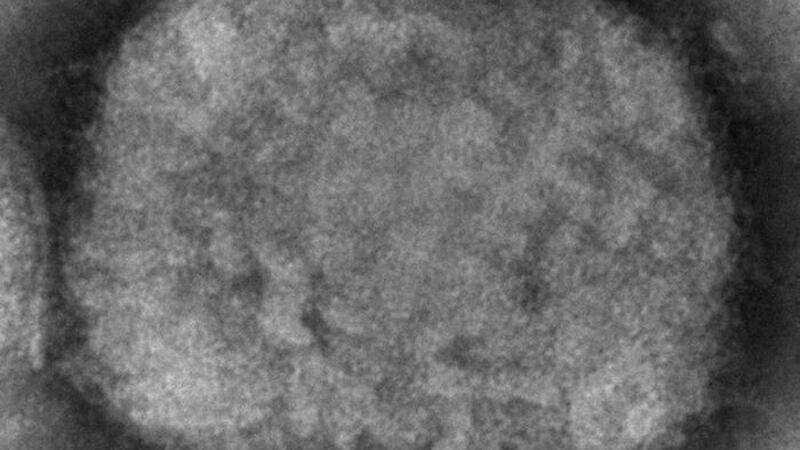

Ambas viruelas son causadas por virus de la misma familia (orthopovirus), y se calcula que la vacuna contra la viruela convencional tiene una eficacia del 85 por ciento contra la del mono, aunque es posible que ese porcentaje haya bajado debido al largo tiempo en la que la mayoría de las personas fueron inoculadas hace décadas.

El experto subrayó que se cree que el principal origen de esta enfermedad zoonótica (que se transmite de animales al hombre) parece estar en las ardillas y otros roedores, por lo que su actual nombre de “viruela del mono” es cuestionable.

La enfermedad se bautizó así al ser primero detectada hace más de medio siglo por investigadores en Copenhague, la capital danesa, que la identificaron en monos procedentes de Singapur.